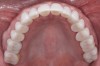

Fig 8. Maxillary occlusal view of cemented anterior full-contour high-translucent zirconia crowns and refined conservative preparations of posterior teeth for onlays and crowns.

Figure 8

A 40-year-old patient presented with the chief complaint: “My teeth are cracking, and I would like to have my original bite.” Dental findings included Class I occlusion with slight misalignment between teeth Nos. 8 and 9. Generalized severe occlusal wear and slight Class I mobility of teeth Nos. 23 to 26 were noted. Caries lesions were found on teeth Nos. 2, 4, 6, 8, 9, and 14 and abfraction lesions on teeth Nos. 4, 5, 10, 11, 13, 20, and 21. Figure 1 through Figure 3 depict the preoperative situation. Full-mouth rehabilitation was suggested. The goals for the restorative treatment were management of erosive etiology, conservation of tooth structure, and long-term protection of the restorations. A diagnostic wax-up was instrumental in determining functional and esthetic treatment goals and establishing new anterior guidance (Figure 4). A comprehensive, step-by-step treatment approach was applied, which, after periodontal pretreatment, caries control, and provisionalization, included definitive preparation (Figure 5) and restoration of the maxillary anterior teeth to establish anterior occlusal guidance. CAD/CAM–fabricated full-contour monolithic high-translucent zirconia crowns (Katana™ UTML Ultra Translucent Multi-Layered, Kuraray Noritake Dental, kuraraynoritake.com) were fabricated (Figure 6 and Figure 7) and cemented with self-adhesive resin cement (Panavia SA, Kuraray Noritake Dental). Figure 8 demonstrates the cemented anterior crowns and refined conservative preparations of posterior teeth, which were performed with minimal tooth-structure removal. High-translucent monolithic zirconia onlays and crowns were fabricated (Katana Zirconia UT, Kuraray Noritake Dental) (Figure 9 to Figure 12). The posterior restorations were adhesively bonded following the APC zirconia-bonding concept. APC-Step A involved air-particle abrasion with 50-μm aluminum oxide at 1.5 bar with a chairside microetcher (Figure 13), followed by application (APC-Step P, Figure 14) of a special ceramic primer (ClearfilTM Ceramic Primer, Kuraray Noritake) with adhesive phosophate monomers (MDP). Relative moisture and contamination control was achieved with cotton rolls and retraction cords. Rubber dam placement, which is always preferred, was difficult in this situation. The enamel surfaces of the abutment teeth were selectively etched (Figure 15) with 35% phosphoric acid (K-Etchant Gel, Kuraray Noritake Dental) and the dentin conditioned (Figure 16) with a self-etch dentin primer (Panavia V5 Tooth Primer, Kuraray Noritake Dental). A dual-cure adhesive resin (Panavia V5 Paste Universal, Kuraray Noritake Dental) was dispensed directly into the restorations with an automix syringe. The restorations were inserted, and excess cement was carefully removed (Figure 17 and Figure 18) before light polymerization (Figure 19). Postoperative views depict the treatment outcome (Figure 20 to Figure 22).